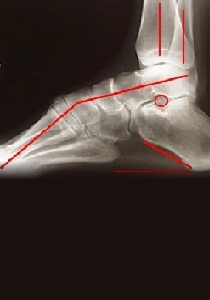

Over-pronation, or flat feet, is a common biomechanical problem that occurs in the walking process when a person’s arch collapses upon weight bearing. This motion can cause extreme stress or inflammation on the plantar fascia, potentially causing severe discomfort and leading to other foot problems.

Over-pronation is very prominent in people who have flexible, flat feet. The framework of the foot begins to collapse, causing the foot to flatten and adding stress to other parts of the foot. As a result, over-pronation, often leads to Plantar Fasciitis, heel spurs, metatarsalgia, post-tib tendonitis and/or bunions. There are many causes of flat feet. Obesity, pregnancy or repetitive pounding on a hard surface can weaken the arch leading to over-pronation. Often people with flat feet do not experience discomfort immediately, and some never suffer from any discomfort at all. However, when symptoms develop and become painful, walking becomes awkward and causes increased strain on the feet and calves.

Over-Pronation can be treated conservatively (non-surgical treatments) with over-the-counter orthotics. These orthotics should be designed with appropriate arch support and medial rearfoot posting to prevent the over-pronation. Footwear should also be examined to ensure there is a proper fit. Footwear with a firm heel counter is often recommended for extra support and stability. Improperly fitting footwear can lead to additional foot problems.